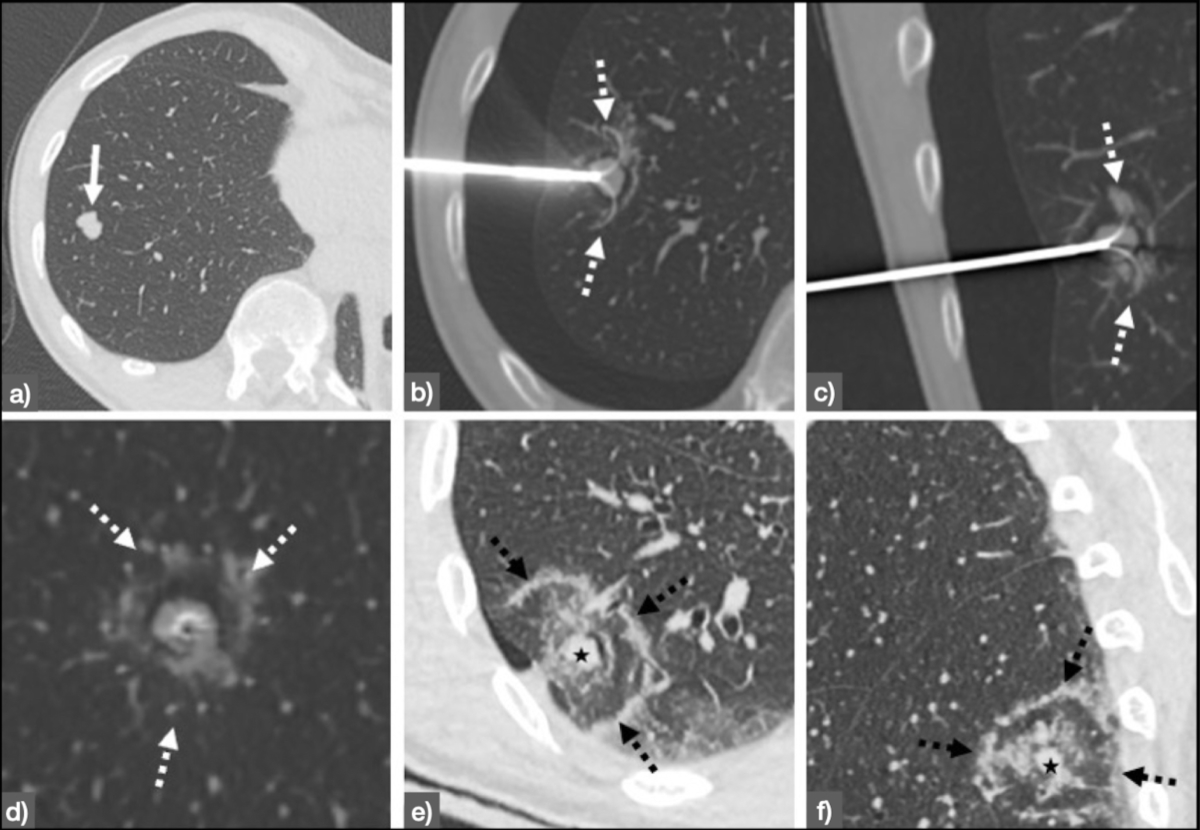

In thermal ablation, tissue destruction is achieved either through application of heat or cold. The most studied technique so far is radiofrequency ablation (figure 3). Other thermal ablative techniques include microwave ablation and cryoablation, both with comparable results to radiofrequency ablation [56, 60]. Cryoablation in particular has shown promising results in recent years with the multicentre, prospective SOLSTICE trial and long-term results by the prospective ECLIPSE trial with local tumour control rates of 85–90% [61, 62]. One of the main advantages of cryoablation is the painless ablation technique, which makes general anaesthesia obsolete [63]. In addition, pleural tumours can be treated without postoperative pain. Further comparative studies have to be performed to compare the effectiveness of the two techniques.

Figure 3Radiofrequency ablation of histologically proven early-stage (Stage IA) non-small cell lung cancer [46] in a 65-year-old patient. Panel A shows the planning CT depicting the tumour (white arrow) before intervention. Panels B (axial), C (sagittal) and D (coronal) show the deployable radiofrequency ablation (RFA) needle (LeVeen 3.5 cm, Boston Scientific, Natick, MA, USA) in place covering the entire lesion (white dotted arrows). Panels E (axial) and F (coronal) show the control scan immediately after the procedure, in which the ablation margin (black dotted arrows) is clearly visible with sufficient distance to the treated tumour (black star). After one year, no signs of local recurrence were detected.